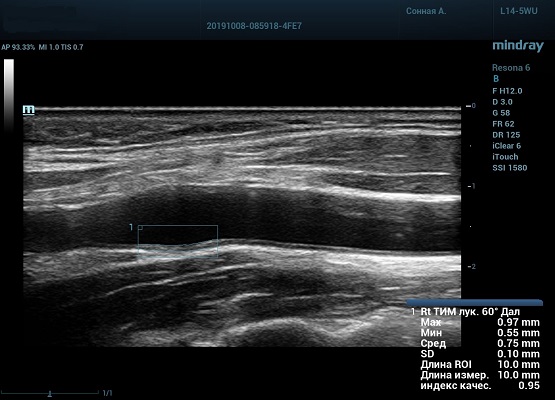

На сегодняшний день измерение IMT происходит автоматическим путем при использовании функции AUTO-IMT. Необходимо указать прибору зону интереса, стандартной длиной (1 см), в которой происходит отслеживание кромок и выдача максимального, среднего и минимального значения.

УЗИ аппараты компании Mindray среднего, экспертного и премиального класса снабжены данной функцией и позволяют контролировать не только полученные значения, но и оценить точность измерения кромки в конкретной зоне по индексу качества. Используя индекс качества, легко решить, можно ли использовать полученное значение.